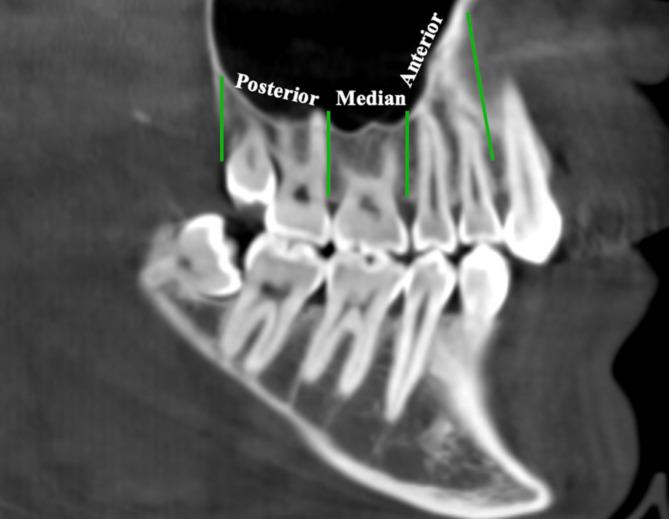

Nine hundred thirty-nine maxillary posterior segment images from 527 subjects were retrospectively scanned via CBCT. A total of 826 premolar, 701 first molar and 817 s molar teeth were examined. The maxillary sinuses in each segment were divided into anterior, median and posterior regions according to the tooth roots they were associated with, and their membrane thicknesses were measured and categorized. The effects of age and gender on membrane thickness were evaluated. T tests and one-way ANOVA were used to analyze differences between groups, followed by post hoc Tukey tests for multiple comparisons. Additionally, correlation analyses were performed to investigate the relationships between the categorized membrane thicknesses and periodontal bone loss.

回顾性扫描了来自527名受试者的939张上颌后段图像。共检查了826颗前磨牙、701颗第一磨牙和817颗第二磨牙。每个节段的上颌窦根据与其相关的牙根分为前部、中部和后部区域,并测量其膜厚度并进行分类。评估年龄和性别对膜厚度的影响。使用t检验和单因素方差分析来分析组间差异,随后进行事后Tukey检验以进行多重比较。此外,进行相关性分析以研究分类后的膜厚度与牙周骨丧失之间的关系。